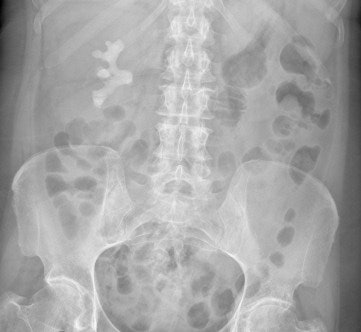

En la mayoría de los departamentos de urgencias, la radiografía abdominal constituye una parte importante de la evaluación médica de pacientes que presentan un dolor abdominal agudo, pero una radiografía abdominal anormal es notoriamente difícil de interpretar y los rayos X abdominales normales son engañosos porque pueden dejar pasar varias condiciones. Esta situación está haciendo que muchos hospitales rectifiquen sus procedimientos.

La radiografía abdominal es una investigación clínica estándar, pero no es sensible ni específica en el manejo del abdomen agudo, de acuerdo a Yamamoto. Independientemente de los resultados de la radiografía abdominal, en cerca de la mitad de los pacientes se tendrán que obtener imágenes adicionales por TC y ultrasonido, de las cuales un gran porcentaje generalmente son anormales. Estos exámenes de imágenes se realizan en promedio más de 24 horas después de la presentación inicial. Durante este tiempo, los pacientes dejan el departamento de urgencias y son admitidos a salas hospitalarias, lo cual tiene implicaciones en los costos para admisiones no ambulatorias y ejerce presión sobre los recursos.

"La radiografía abdominal juega un papel limitado en la evaluación de pacientes con abdomen agudo y debe ser reemplazada por otras modalidades. La TC y la sonografía son más sensibles y ofrecen una mayor probabilidad de un diagnóstico correcto," concluyó Yamamoto. "El riesgo es que la radiografía abdominal pueda ser simplemente reemplazada por la TC y, con este fin, los pacientes remitidos están siendo monitoreados."